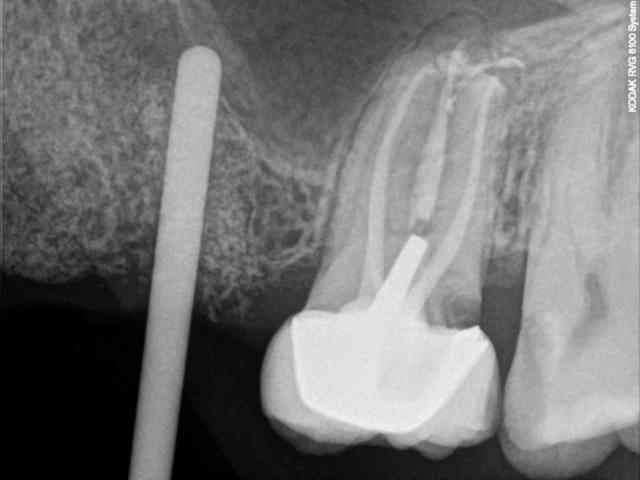

7-8-9-10-11- les radios